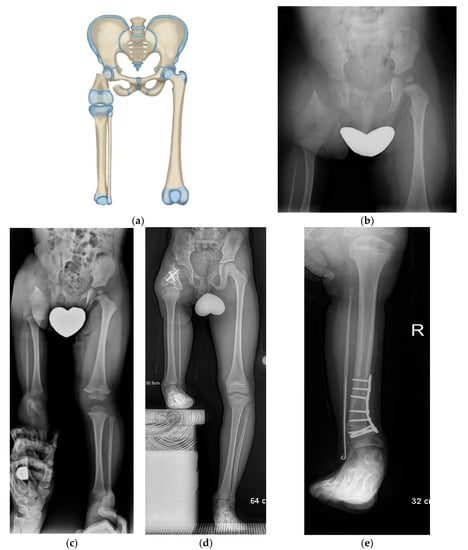

Figure 3.

(a) Paley–Brown Rotationplasty illustration for Paley type 3 (a or b), (b) AP pelvis radiograph in 3-year-old girl with Paley type 3a CFD, (c) Standing long radiograph showing the left ankle is at the level of the right knee, (d) Standing long radiograph two years after Paley–Brown rotationplasty. The ankle is at the level of the opposite distal femoral physis (level of knee center of rotation). Clinically she has excellent gait and function.